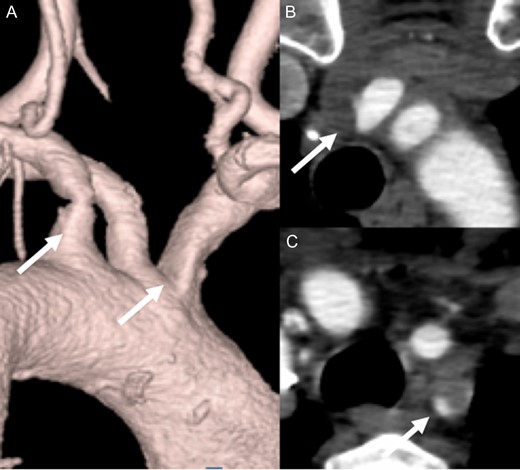

A 65-year-old woman admitted to a territorial hospital due to dizziness and listless feeling in the left arm. Magnetic resonance imaging revealed multiple CIs in the right frontal area and cerebellum on both sides (Fig. 1). Computed tomography angiography (CTA) detected stenosis in the IA and LSA (Fig. 2). No atrial fibrillation was detected despite repeated Holter-Electrocardiography. The patient was initially treated with aspirin, but thereafter experienced recurrent CIs. Clopidogrel was therefore added. Under double anti-platelet therapy, she suffered further CIs, and warfarin was added. However, CI occurred yet again. After six CIs, she was referred to our hospital.

After admission, carotid ultrasonography revealed a large, soft plaque with ulceration in the IA and a very mobile soft plaque in the LSA (Fig. 3). EVT was thus considered too dangerous, and TAR using a four-branched prosthesis was planned. Intraoperatively, bilateral axillary arteries were initially exposed, and an 8-mm vessel prosthesis was anastomosed. Median sternotomy was then performed. Cardiopulmonary bypass was established with arterial perfusion via bilateral axillary arteries and bicaval venous drainage. TAR was performed under hypothermic circulatory arrest with antegrade selective cerebral perfusion, then the brachiocephalic artery and LSA were clamped and the left common carotid artery (LCA) was intubated. To avoid hoarseness due to injury of the left recurrent laryngeal nerve, a hybrid prosthesis (FROZENIX, Japan Lifeline, Tokyo, Japan) was used and a distal anastomosis was created between the LCA and LSA. The LCA was ligated and the prosthesis, which was anastomosed to the left axillary artery, was brought into the mediastinum and anastomosed with a branch of the four-branched prosthesis (Fig. 4). The postoperative course was uneventful and the patient was discharged on postoperative day 16 (Fig. 5).

A soft plaque with ulceration in the IA (A, B) and a very mobile soft plaque in the LSA (C, D).